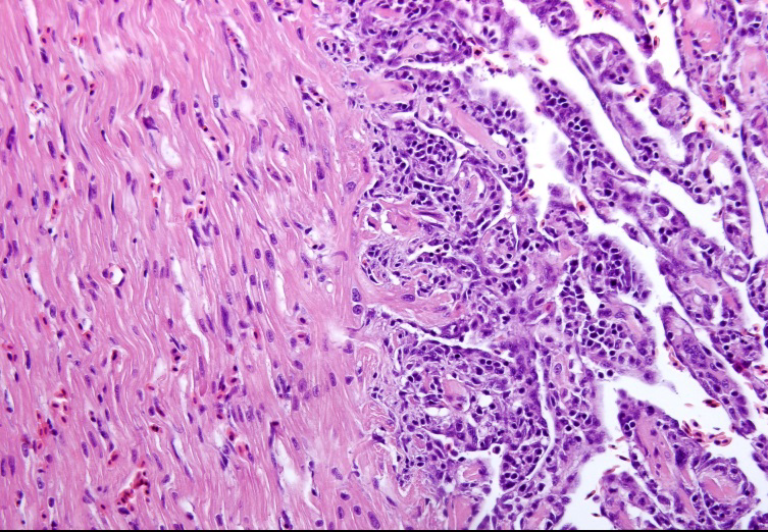

Histopatologisk karakteriseres CMS av betennelse og fortykket endokard (cellelaget som kler hjertets innside) og nekrose i muskelceller i spongiøst myokard (hjertets indre, svampaktige muskellag). Forandringene sees først i atriet (forkammeret), før de brer seg videre til ventrikkelen (hjertekammeret) [22] (Figur 4). Betennelsescellene er hovedsaklig mononukleære celler, sannsynligvis lymfocytter og makrofager, som først påvises subendokardialt (rett under endokardlaget på hjertes indre muskeloverflater) før også muskellaget innenfor infiltreres. I alvorlige tilfeller av CMS kan det utvikles en cellerik epikarditt (betennelse) på hjertets ytterflate. Hjerteventrikkelens kompakte muskellag (kompaktum) er som regel uten betennelsesforandringer, men betennelsesceller fra en epikarditt kan bre seg innover i kompaktumlaget langs større blodkar i tilfeller med uttalte CMS-forandringer [23]. Kraftige betennelsesforandringene er årsaken til at forkammerveggen og/eller veggen i sinus venosus blir svekket og kan briste, med blod i hjertesekken (hjertetamponade) og brå død som resultat. Forkammerforandringene er som regel mer uttalte enn forandringene i hjertekammeret, og hjertesvikten med påfølgende alvorlig stuvning kan gi CMS-relaterte forandringer også i andre indre organer som lever og milt.

Figur 4: Typiske histopatologiske funn ved CMS: Figur 4a) viser den tydelige forskjellen mellom normalt vev i hjerteventrikkelens kompakte muskellag (mot venstre i bildet) og uttalte CMS-forandringer med rikelig infiltrasjon av betennelsesceller i det indre, spongiøse muskellaget (mot høyre i bildet). Figur 4b) Høy forstørrelse av langt framskredne, klassiske CMS-forandringer i spongiøs hjertemuskel. Noen steder kun betennelsesceller innenfor endotelcellelaget som kler muskeloverflaten, og andre steder kun rester av hjertemuskulaturen (lys rosa) igjen, iblandet betennelsesceller. Foto. T.T. Poppe.